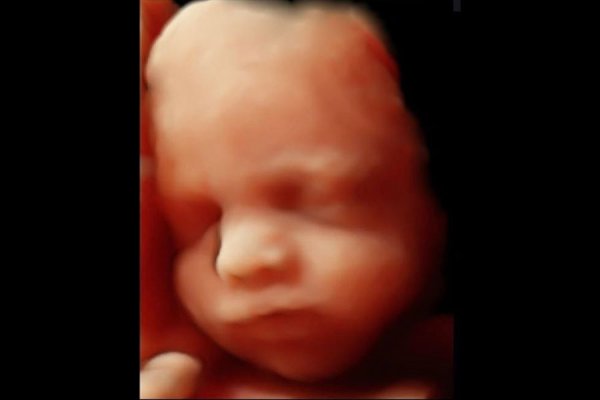

Gebelik sürecinde bebeğinizin gelişimini takip etmek en büyük heyecanınızdır. 3 boyutlu ultrason (3D) ve 4 boyutlu ultrason (4D), bu heyecanı bir adım öteye taşıyarak bebeğinizin yüz hatlarını ve hareketlerini gerçekçi bir şekilde görmenizi sağlayan gelişmiş bir görüntüleme teknolojisidir.

3 Boyutlu Ultrason (3D): Bebeğinizin fotoğrafını çeker. Yüz hatlarının, burnunun, dudaklarının ve elmacık kemiklerinin üç boyutlu ve sabit bir görüntüsünü elde edersiniz.

4 Boyutlu Ultrason (4D): Bebeğinizin videosunu çeker. Üç boyutlu görüntüye hareket (zaman) boyutu eklenir. Bebeğinizin esnemesini, gülümsemesini, elini yüzüne götürmesini veya parmağını emmesini canlı olarak izleyebilirsiniz.